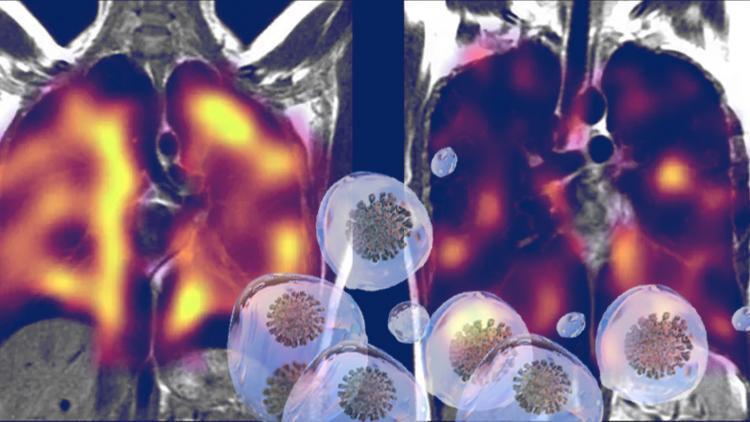

İngiltere'de yapılan küçük çaplı bir pilot çalışma, 'uzun kovid'li bazı kişilerin akciğerlerinde gizli hasar olabileceğini gösteriyor.

Araştırmacılar, rutin taramalarla tanımlanamayan akciğer anormalliklerini tespit etmek için ksenon (zenon) gazı ile yeni bir tarama yöntemi kullandılar.

Tüm katılımcılar, bir manyetik rezonans görüntüleme (emar-MR) taraması sırasında ksenon gazı soludu.

Ksenon gazı, oksijene benzer şekilde davranıyor, ancak taramalar sırasında görsel olarak izlenebiliyor.

Böylece araştırmacılar, bu gazın akciğerlerden kan dolaşımına ne kadar iyi geçtiğini gözlemleyebildiler; zira bu geçiş, oksijenin vücutta taşınmasında çok önemli bir aşama olarak görülüyor.

Araştırmacılar, uzun süreli kovid hastası olan kişilerin çoğunluğu için gaz transferinin, sağlıklı kişilerden oluşan kontrol grubuna göre daha az etkili olduğunu gördü.